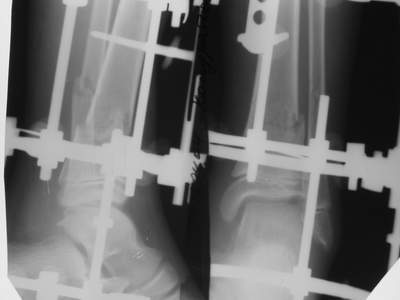

Нашел в комп-ре схожий случай:

1) з/репозиция, 2) фиксация 2 спицами, 3) аппарат, 4) фиксационные

спицы удалены...

См. аттачт.

А можно было наложить аппарат и по поводу ложного сустава...

По крайней мере не было бы укорочения (пусть и в 2 см)...